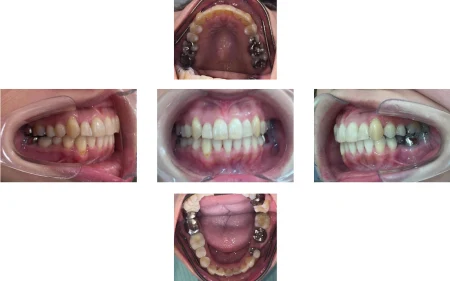

歯が綺麗に並び、見た目と噛み合わせが改善しました。

患者様にも「自信を持って笑えるようになりました」と大変ご満足いただいています。

今後、銀歯の部分を白く丈夫な「セラミック」に変えていく予定です。